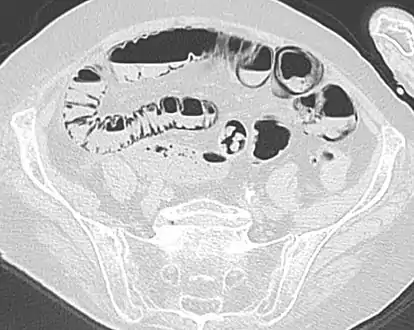

Pneumatosis intestinalis in computed tomography with intestinal ischemia. Lung window for better representation of the gas deposits in the intestinal walls.

Coronal reformatted MDCT image showing extensive pneumatosis intestinalis in the left upper quadrant small bowel. The pneumatosis is more cystic and nodular in the small bowel in the midline and the right of midline. This patient had a relatively benign presentation without bowel ischemia and was treated conservatively.